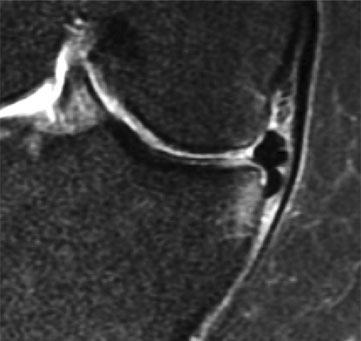

3. Gutter fragment

A torn meniscal fragment can displace & sit in the medial gutter, causing stubborn joint line pain

Similar clinical pattern to 2.

Focal tibial lip bone oedema on MRI is the give away

Consider arthroscopy - chondral erosion can occur otherwise